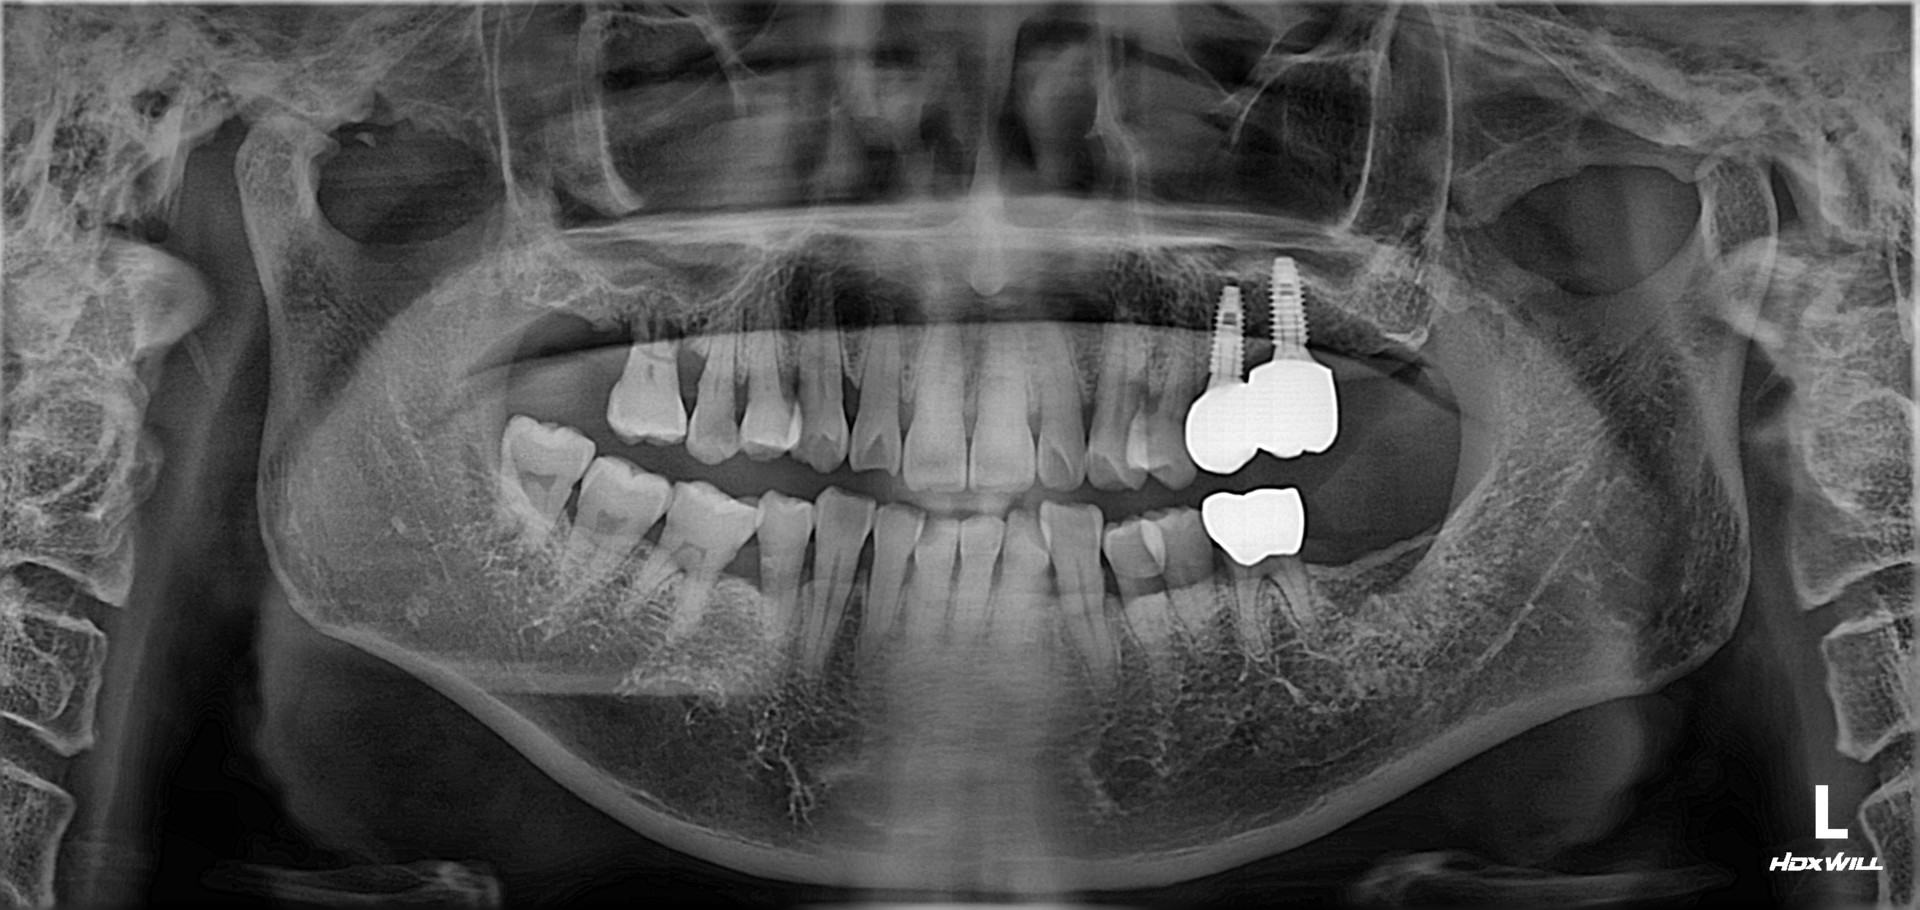

상악동 거상술 및 임플란트 식립

치료 기간 2023. 12. 21(치료 당일)

아래 치료는 상악동 거상술 및 임플란트 식립에 대한

치료 당일에 대한 설명입니다.

우측 상악 잔존골이 얼마 없는 난이도가 있는 수술이지만, 참조은치과에서는 수술시간이 15분 정도 소요되었습니다. 근육주사를 이용하여 붓기 조절 및 염증 조절도 시행하였습니다.

참조은치과 전속 기공사 선생님들이 상주하여 모든 임플란트를 지르코니아로 제작 중이며, 인접면 처리 및 교합조정이 바로 가능합니다.

아래 치료는 상악동 거상술 및 임플란트 식립에 대한 치료 당일에 대한 설명입니다.

우측 상악 잔존골이 얼마 없는 난이도가 있는 수술이지만, 참조은치과에서는 수술시간이 15분 정도 소요되었습니다.

근육주사를 이용하여 붓기 조절 및 염증 조절도 시행하였습니다.

참조은치과 전속 기공사 선생님들이 상주하여

모든 임플란트를 지르코니아로 제작 중이며, 인접면 처리 및 교합조정이 바로 가능합니다.